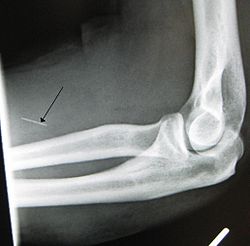

The preferred injection site is the crook of the elbow (i.e., the Median cubital vein), on the user's non-writing hand. Other users opt to use the Basilic vein; while it may be easier to "hit", caution must be exercised as two nerves run parallel to the vein, increasing the chance of nerve damage, as well as the chance of an arterial "nick".[5]